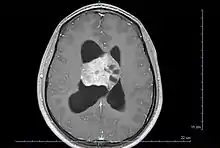

| Axial T1-weighted gadolinium-enhanced MRI image showing an enhancing mass with cystic changes consistent with central neurocytoma in the right lateral ventricle. | |